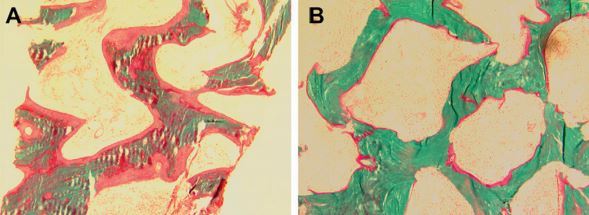

Title: Vitamin D Deficiency Osteomalacia Before (A) and After (B) Treatment with Vitamin D

- Caption: Bone histomorphometry in the Case Vignette. Note wide and extensive osteoid before treatment (A) and almost complete disappearance of osteoid after treatment (B ).